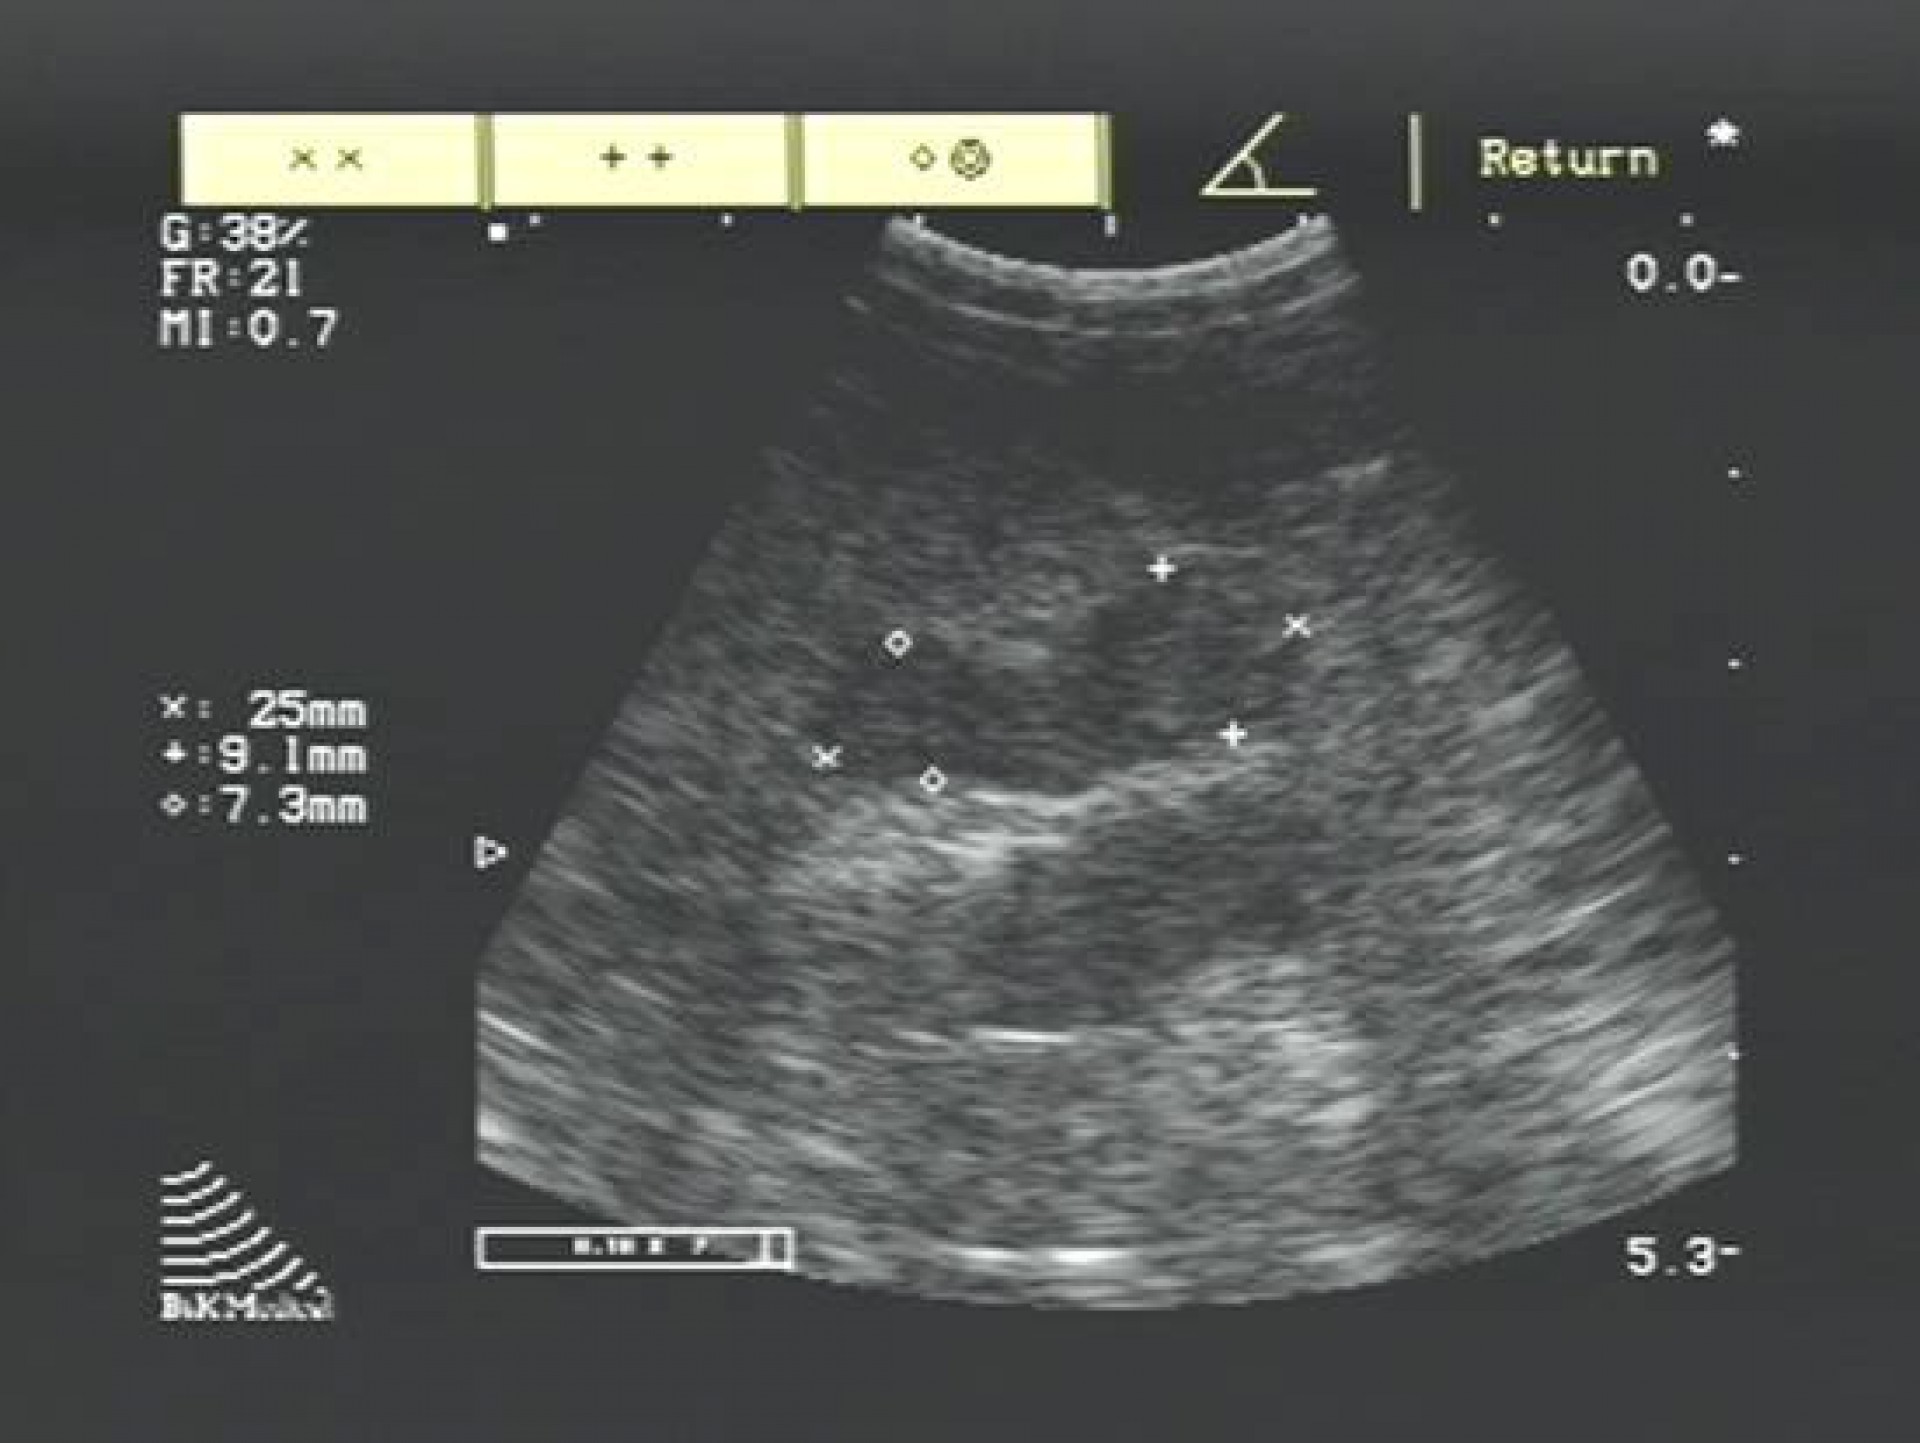

A betegség diagnosztizálása hasüregi ultrahangos vizsgálattal és vérvizsgálattal történik, mely során különös figyelmet kell fordítani a perifériás és centralis forma elkülönítésére.